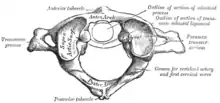

Anterior arch

The anterior arch forms about one-fifth of the ring: its anterior surface is convex, and presents at its center the anterior tubercle for the attachment of the Longus colli muscles and the anterior longitudinal ligament; posteriorly it is concave, and marked by a smooth, oval or circular facet (fovea dentis), for articulation with the odontoid process (dens) of the axis.

The upper and lower borders respectively give attachment to the anterior atlantooccipital membrane and the anterior atlantoaxial ligament; the former connects it with the occipital bone above, and the latter with the axis below.[5]

Posterior arch

The posterior arch forms about two-fifths of the circumference of the ring: it ends behind in the posterior tubercle, which is the rudiment of a spinous process and gives origin to the Recti capitis posteriores minores and the ligamentum nuchae. The diminutive size of this process prevents any interference with the movements between the atlas and the skull.

The posterior part of the arch presents above and behind a rounded edge for the attachment of the posterior atlantooccipital membrane, while immediately behind each superior articular process is the superior vertebral notch (sulcus arteriae vertebralis). This is a groove that is sometimes converted into a foramen by ossification of the posterior atlantooccipital membrane to create a delicate bony spiculum which arches backward from the posterior end of the superior articular process. This anatomical variant is known as an arcuate foramen.

This groove transmits the vertebral artery, which, after ascending through the foramen in the transverse process, winds around the lateral mass in a direction backward and medially to enter the vertebrobasilar circulation through the foramen magnum; it also transmits the suboccipital nerve (first spinal nerve)

On the under surface of the posterior arch, behind the inferior articular facets, are two shallow grooves, the inferior vertebral notches. The lower border gives attachment to the posterior atlantoaxial ligament, which connects it with the axis.

Lateral masses

The lateral masses are the most bulky and solid parts of the atlas, in order to support the weight of the head.

Each carries two articular facets, a superior and an inferior.

- The superior facets are of large size, oval, concave, and approach each other in front, but diverge behind: they are directed upward, medially, and a little backward, each forming a cup for the corresponding condyle of the occipital bone, and are admirably adapted to the nodding movements of the head. Not infrequently they are partially subdivided by indentations which encroach upon their margins.

- The inferior articular facets are circular in form, flattened or slightly convex and directed downward and medially, articulating with the axis, and permitting the rotatory movements of the head.

Vertebral foramen

Just below the medial margin of each superior facet is a small tubercle, for the attachment of the transverse atlantal ligament which stretches across the ring of the atlas and divides the vertebral foramen into two unequal parts:

- the anterior or smaller receiving the odontoid process of the axis

- the posterior transmitting the spinal cord (medulla spinalis) and its membranes

This part of the vertebral canal is of considerable size, much greater than is required for the accommodation of the spinal cord.

Transverse processes

The transverse processes are large; they project laterally and downward from the lateral masses, and serve for the attachment of muscles which assist in rotating the head. They are long, and their anterior and posterior tubercles are fused into one mass; the foramen transversarium is directed from below, upward and backward.